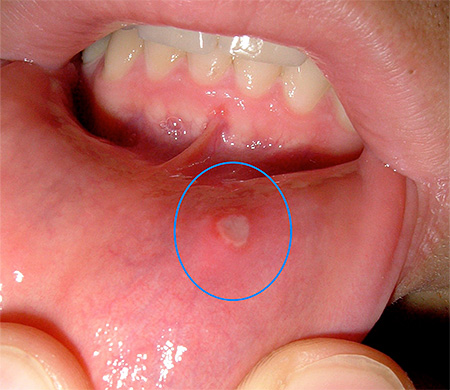

Высыпания представляют собой одиночные или располагающиеся группами пузырьки разного размера, в том числе и довольно крупные, с прозрачной жидкостью внутри (в этой жидкости в буквальном смысле слова миллиарды вирусных частиц). Вскоре жидкость мутнеет, везикула лопается, образуя эрозию. Эрозии долго не заживают и превращаются в язвочки, покрытые белесым налетом или пленочкой.

На мягких участках слизистой язвочки видны хорошо, а на твердых деснах выглядят мелкими точками. В тяжелых случаях могут образовываться некротические язвы.